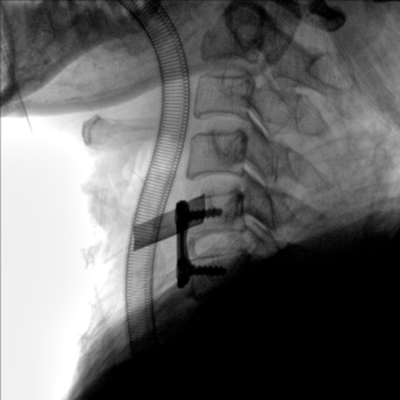

動態板C形臂 開啟清晰影像新篇章

大尺寸動態平板探測器,高DQE、低噪聲、圖像清晰。采用多分辨率圖像增強處理技術,不同部位不同圖像處理算法,滿足客戶多樣化的需求。